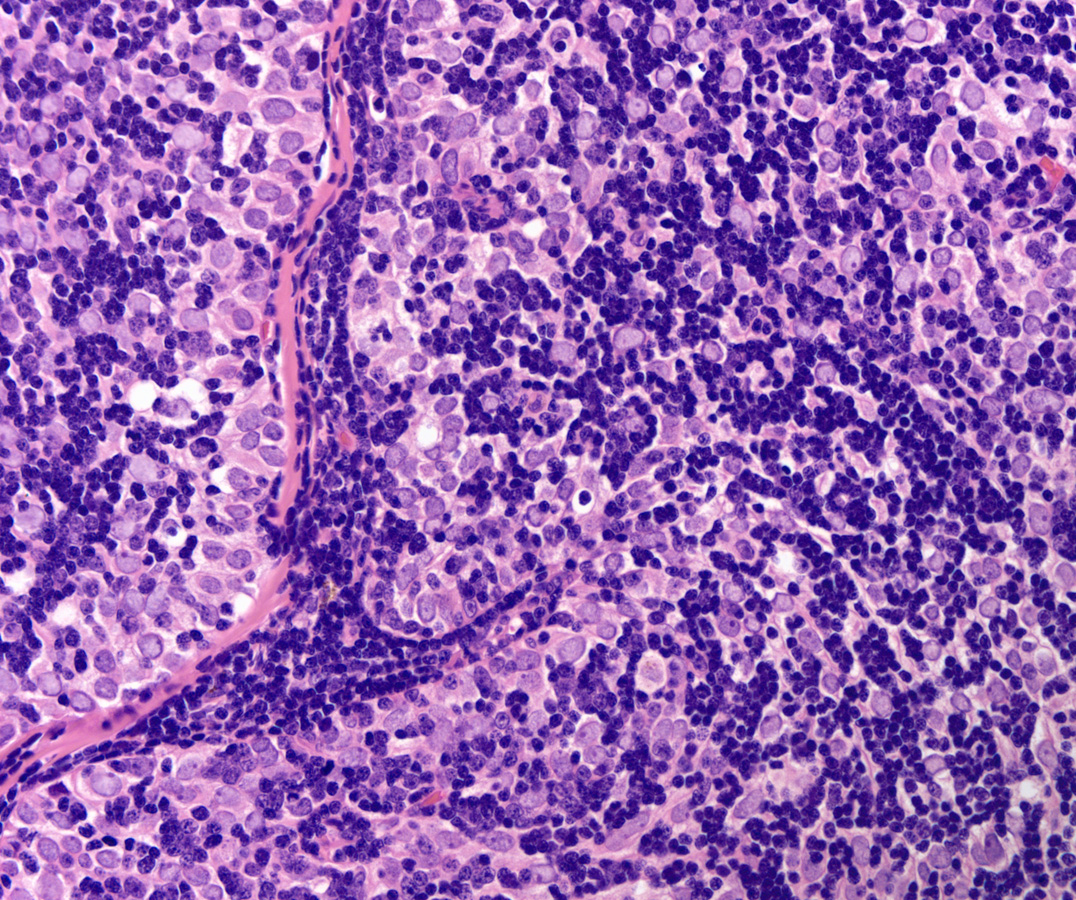

Low power H&E show tumor in below the mesothelial lining. Distinct lobular / organoid appearance noted with two types of cells, small lymphoid cells and large neoplastic cells with clear cytoplasm (bi-phasic pattern). IHC stains showed large cells are cytokeratin positive and small lymphoid cells expressed CD3, CD5 and ntDt (immature thymocytes).

Additional history later revealed a large anterior mediastinal mass with tracheal compression and seeding of pleura. Main tumor was not resectable. Histology (epithelial elements and thymic lymphoid stroma) and IHC stains support an aggressive thymoma, WHO B2, metastatic to pleura. Normal thymic milieu i.e. immature thymocytes often present in metastasis along with neoplastic epithelial component. Metastatic thymoma must be considered in the differential diagnosis with bi -phasic patten as illustrated above.